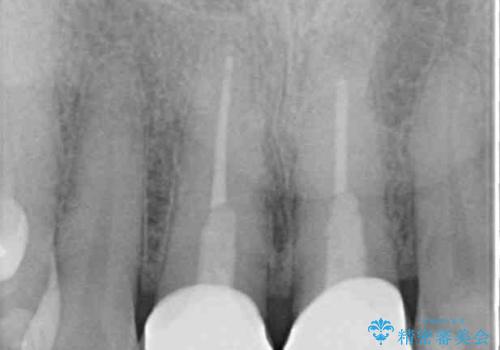

- 変色した保険の前歯のクラウンを交換したいとのことで来院された患者様です。

中心左側の歯はクラウンが装着されており、右側は神経組織が除去されて多少変色している状態でした。

右側の歯も将来的にもっと変色する可能性があるため、前歯2本をオールセラミッククラウンにて補綴治療を行うこととしました。